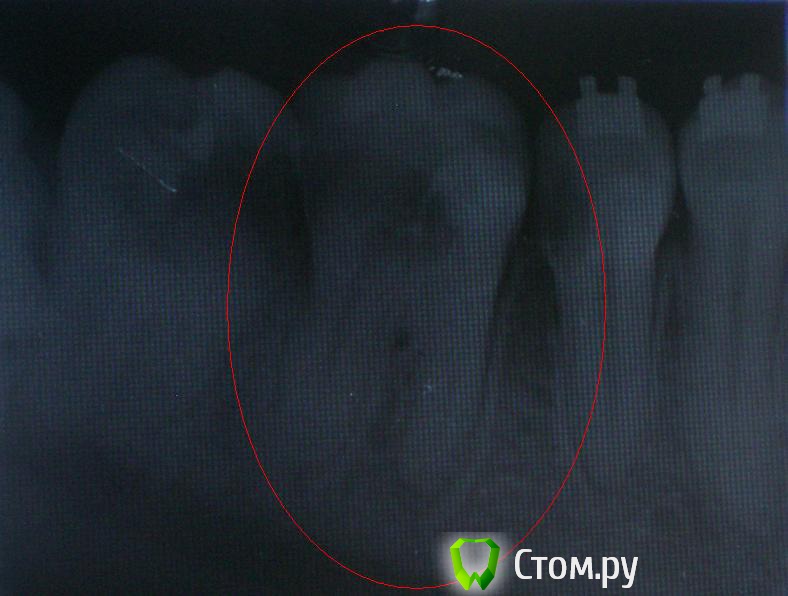

ВикторияВолк Опубликовано 1 июля, 2014 Поделиться Опубликовано 1 июля, 2014 около полугода назад, из него удалили нерв. запломбировали, все было хорошо, но на прошлой неделе начал очень сильно болеть, болели и оба соседних зуба, челюсть, и в ухо отдавало. я пришла к врачу, мне открыли канал, я так походила 5 дней, и сегодня мне канал закрыли, поставили лекарство под временную пломбу, теперь опять чуть ноет..снимок делали до того как открыть канал Ссылка на комментарий

diesel87 Опубликовано 1 июля, 2014 Поделиться Опубликовано 1 июля, 2014 Здравствуйте, снимок плохого качества, единственное что можно сказать, что в каналах 6ого зуба материала не особо прослеживается и болеть так же может 7-ой зуб. Ссылка на комментарий

DokDent Опубликовано 1 июля, 2014 Поделиться Опубликовано 1 июля, 2014 около полугода назад, из него удалили нерв. запломбировали, все было хорошо, но на прошлой неделе начал очень сильно болеть, болели и оба соседних зуба, челюсть, и в ухо отдавало.Всё правильно. Все 3 зуба нуждаются в лечении Ссылка на комментарий